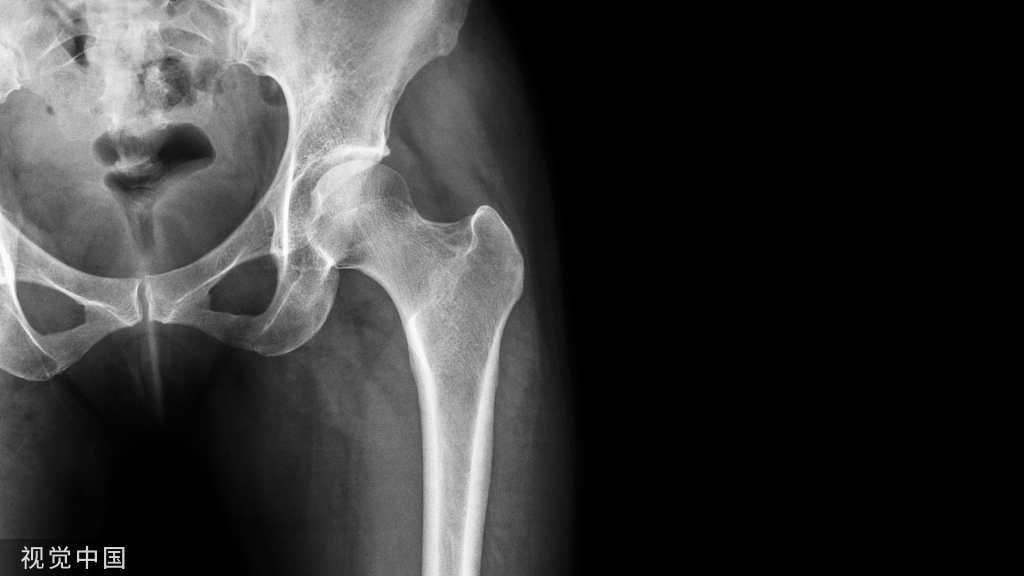

15、骨盆的软骨连接:骨盆由髂骨、坐骨和耻骨构成,未形成骨性连接之前表现为透亮线。